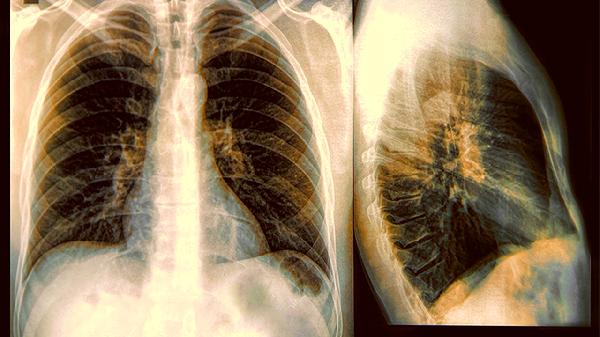

变异性哮喘患者为何常出现大量白色黏痰

变异性哮喘患者常伴随白色黏痰增多,这种情况通常是由气道炎症、持续的过敏原刺激、呼吸道感染、胃食管反流以及环境因素共同作用引起的。通过抗炎治疗、控制过敏、抗感染处理、抑制胃酸以及改善生活环境中的一些措施,可以有效缓解症状。